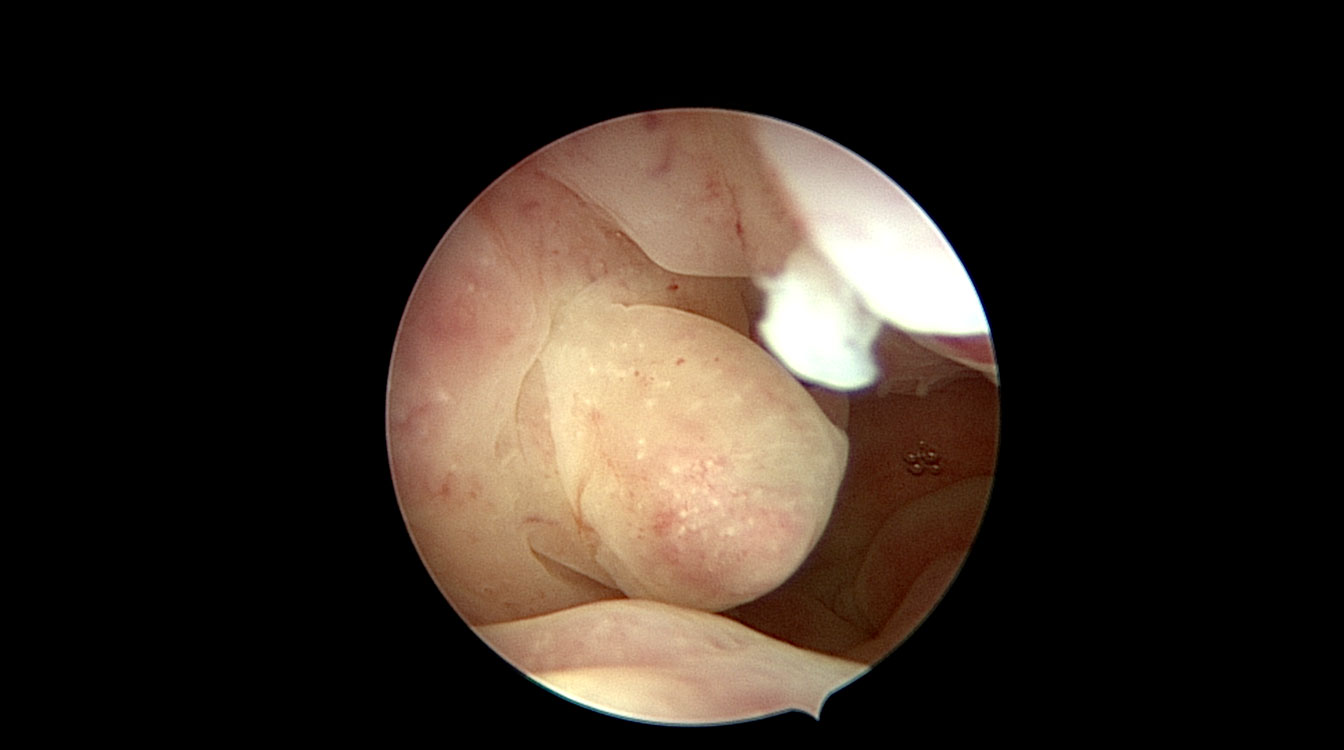

Polipii uterini

Polipii uterini reprezintă proliferări locale ale endometrului (mucoasa ce căptușește cavitatea uterină) și în marea majoritate a cazurilor sunt benigni. Ei pot provoca sângerări anormale, infertilitate sau pot interfera cu implantarea embrionilor în cursul fertilizării in vitro. Polipii endometriali pot fi diagnosticați cu ajutorul ecografiei, iar histeroscopia certifică acest diagnostic. În plus, histeroscopia permite și rezecția și extragerea polipilor endometriali. (fig. 3, 4)